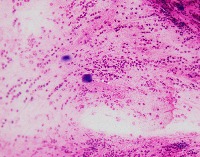

Medical Diagnostics: geckler5 can be used in healthcare facilities to analyze images of tissue samples, blood smear slides, or other medical images to detect the presence and distribution of White Blood Cells (WBC) and Erythrocyte Hemoglobin Concentration (EHC). This can aid in diagnosing diseases such as infections, anemia, or leukemia.

Research and Development: Scientists working in the field of hematology or immunology can use geckler5 to analyze large datasets of blood samples in their research studies. This can help them better understand blood cell morphology, variations, and concentrations in different conditions, ultimately leading to new medical discoveries.

Pharmaceutical Testing: The pharmaceutical industry can utilize geckler5 to analyze the effects of new drugs or treatment methods on WBC and EHC levels. This would allow researchers to monitor the efficacy, side effects, and other critical factors for drug trials and approval processes.

Educational Purposes: Educational institutions teaching medical or biological courses can implement geckler5 as a learning tool, helping students to identify and differentiate between various blood components. This can enhance their understanding of blood cell compositions and related medical conditions.

Blood Donation Centers and Blood Banks: geckler5 can be employed to assess the quality of blood donations in terms of WBC and EHC levels. This automated analysis would help staff ensure that donated blood meets necessary standards and is safe for transfusion into patients.